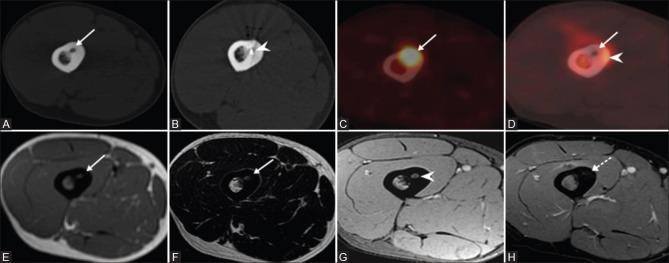

MATERIALS AND METHODS

This is a retrospective analysis of prospectively maintained data of 43 symptomatic osteoid osteoma patients who were treated by radiofrequency ablation (RFA). Forty out of 43 patients were naive cases and underwent primary treatment for osteoid osteoma with RFA, whereas 3 patients included in the study underwent RFA for local recurrence after having undergone surgical treatment. Diagnosis was based on clinical and characteristic imaging findings, and biopsy was done for cases with atypical presentation. Pre and post procedure Visual Analog Score (VAS) was documented in all cases. Monopolar RFA system was used in all patients, and the electrode was placed within the lesion nidus under CT guidance coaxially through 11G introducer needle. Ablation was performed at 90° C for 5 min.

RESULTS

Technical success rate of intranidal placement of electrode was 100%. The primary clinical success in our study was 97.7% (42 of 43), and the secondary clinical success was 100%. Pre and postprocedure VAS score in our study group was 7.8 and 0.4, respectively. Mean follow-up period in our study was 48 months (Range: 4-129 months). One patient had recurrence of pain 4 years after treatment and was treated successfully by a second session. Minor complications were seen in 3 patients with two cases of RF pad burns and one case of skin burn at the treatment site, and these were managed conservatively. No patients developed temporary/permanent neurological deficits, and no procedure-related mortality was seen in our study.

材料与方法

这是一项对43例接受射频消融(RFA)治疗的有症状骨样骨瘤患者的前瞻性维护数据进行的回顾性分析。43例患者中有40例为初发病例,接受了RFA治疗骨样骨瘤的初次治疗,而纳入研究的3例患者在接受手术治疗后因局部复发接受了RFA治疗。诊断基于临床和特征性影像学表现,对于表现不典型的病例进行了活检。所有病例均记录了术前和术后视觉模拟评分(VAS)。所有患者均使用单极RFA系统,电极在CT引导下通过11G穿刺针同轴放置在病变巢内。在90°C下进行5分钟的消融。

结果

电极巢内放置的技术成功率为100%。我们研究中的主要临床成功率为97.7%(43例中的42例),次要临床成功率为100%。我们研究组术前和术后VAS评分分别为7.8和0.4。我们研究的平均随访期为48个月(范围:4 - 129个月)。1例患者在治疗4年后疼痛复发,通过第二次治疗成功治愈。3例患者出现轻微并发症,2例为射频垫烧伤,1例为治疗部位皮肤烧伤,均经保守处理。我们的研究中没有患者出现临时/永久性神经功能缺损,也没有观察到与手术相关的死亡。